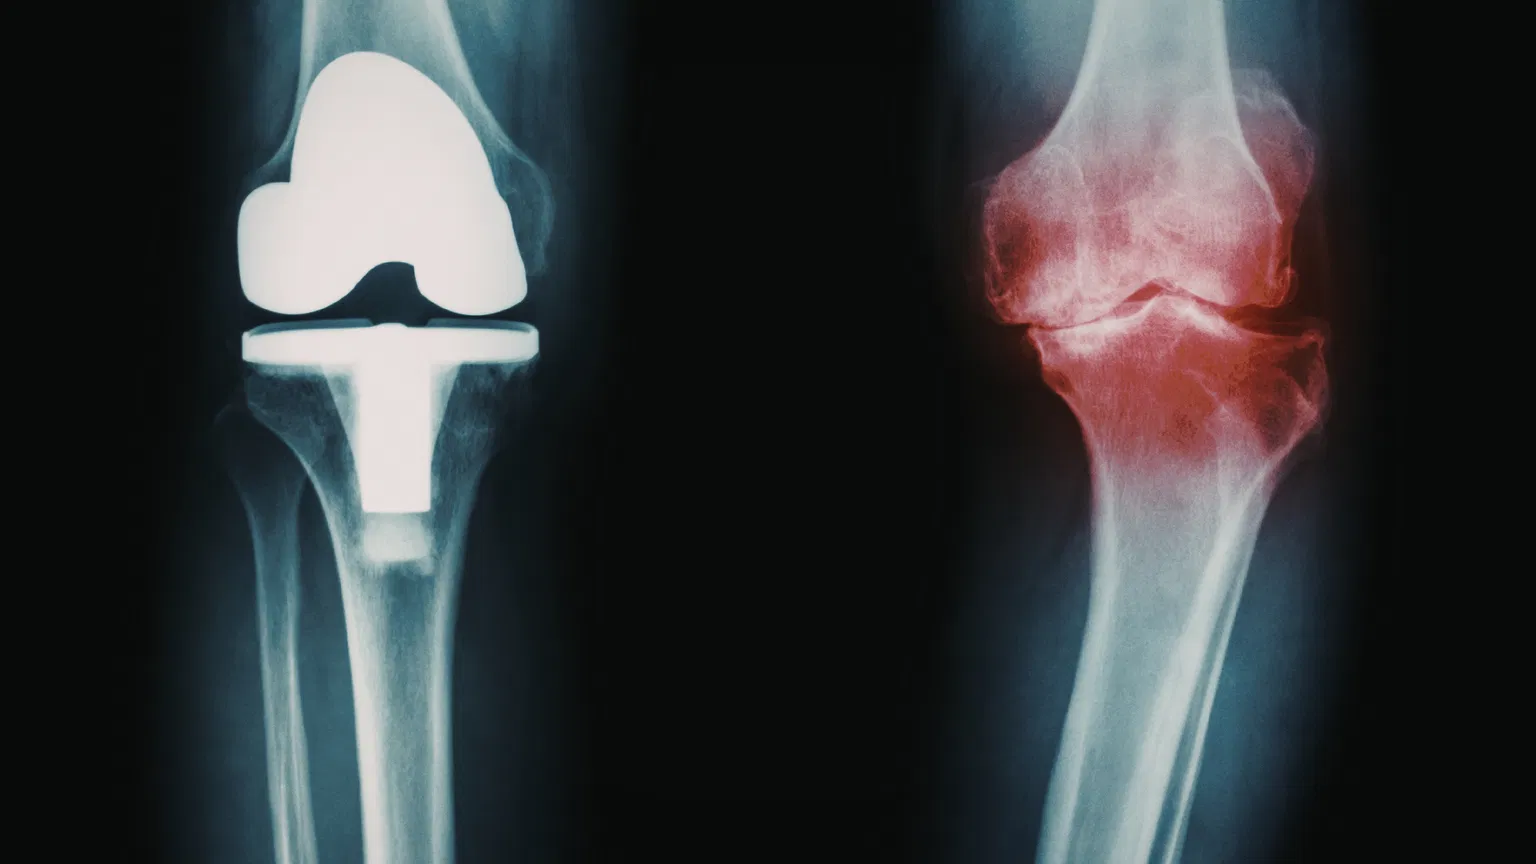

Knee replacement surgery is a procedure in which damaged parts of the knee joint are replaced with artificial components to reduce pain and improve movement.

Arthritis or injury may affect one compartment or multiple compartments. The extent of damage plays a crucial role in deciding whether a partial or total knee replacement is required.

Total knee replacement (TKR) is a procedure in which all damaged surfaces of the knee joint are replaced with artificial implants. It is one of the most common and successful orthopedic surgeries worldwide.

All three compartments of the knee are resurfaced

Total knee replacement is often the best option when knee damage is extensive.